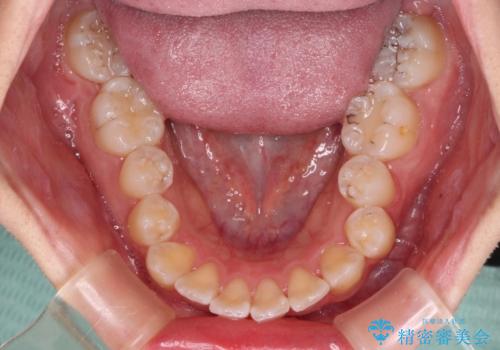

インビザラインでの治療を希望されていましたが、前歯のクロスバイトや下顎小臼歯の捻転が認められたため、インビザライン単独で治療を行うよりも、ワイヤー装置を併用した方が、治療期間の短縮やトラブル回避できると判断し、ワイヤー装置を併用することとしました。

まずはワイヤー装置により前歯のクロスバイトと下顎小臼歯の捻転を改善し、その後インビザラインにより全体を整える矯正治療を行うこととしました。

前歯のクロスバイトは、インビザラインでの改善中に前歯に過剰な力がかかり、歯髄壊死や歯肉退縮を引き起こすことがあります。また下顎小臼歯は寸胴型のため、捻転を排除することが難しいことが知られています。

それをワイヤー装置にて速やかに改善することで、トータルでの治療期間を短くすることができます。